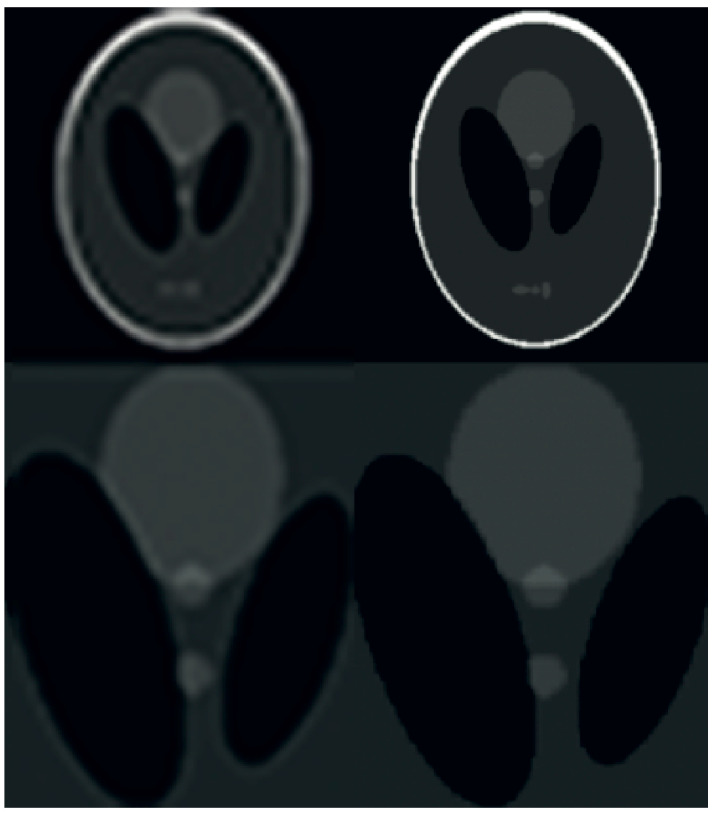

Figure 1.

Thesimplified flowchart of the presented low resolution DW image reconstruction from a compressed sensing k-q spaces. Signals are transferred from layer to layer through the input-output manner.

On the premise that the subject transitions among obtained k-q-space structural components, the subsequent subgroup is linked to patient motion that may be rectified and integrated into a super-resolution algorithm as its fundamental feature, as illustrated in Figure 1.

The low-resolution DW image reconstruction algorithm commences by utilizing k-q-spaces that are highly compressed. The non-uniform fast Fourier transform (NUFFT) is utilized due to the presence of irregular sampling schemes. The subsequent phase utilizes the zero-filling (ZF) methodology.